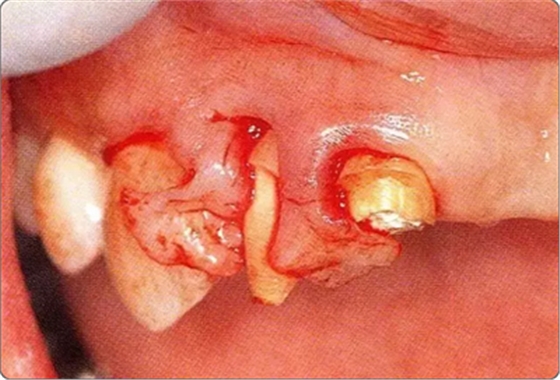

圖10-3 考慮到審美性,應(yīng)用牙齦乳頭保存術(shù)(Papilla preservation technique),進行了自體骨移植。